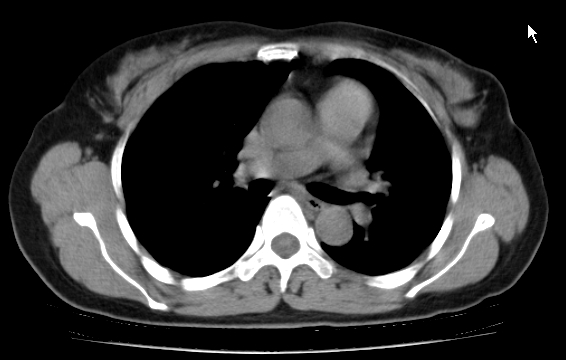

标题: CT25227:背部疼痛伴双侧胸壁痛2月,食欲差。 [打印本页]

标题: CT25227:背部疼痛伴双侧胸壁痛2月,食欲差。

肺结核并胸椎结核?请各位高手指教。

用椎体的条件来扫胸椎呀!考虑1左侧胸膜小结节形成2椎体结核并冷脓肿形成

考虑胸椎结核并椎旁软组织肿胀。

左肺结核灶,胸椎结核并冷脓肿。

支持!不排除骨原发淋巴瘤肺内转移。

食道癌并胸椎及肺内转移